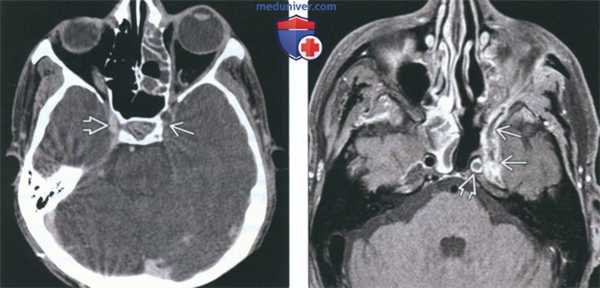

(Слева) На аксиальной МРТ (Т1 ВИ С+) - типичный случай верхнечелюстного грибкового гайморита с распространением в окружающие мягкие ткани, в т.ч. в жевательное пространство, и контрастным усилением жевательных мышц.

(Справа) На аксиальной MPT (Т2 ВИ FS) у этого же пациента определяется гипоинтенсивный сигнал в пазухе, характерный для грибковой инфекции. Обратите внимание на гиперинтенсивный сигнал в пораженных жевательных мышцах.

(Слева) На аксиальной МРТ (Т1 ВИ С+) у пациента, получавшего иммуносупрессоры после трансплантации, определяется инвазивный грибковый синусит с поражением ячеек решетчатого лабиринта справа и распространением инфекции в правую глазницу вокруг прямых мышц и с поражением вершины. Определяются также признаки интракраниального распространения через верхнюю глазничную щель.

(Справа) На корональной МР (Т2 ВИ) у этого же пациента в верхних внутренних отделах глазницы определяется гипоинтенсивный сигнал, характерный для грибкового поражения.